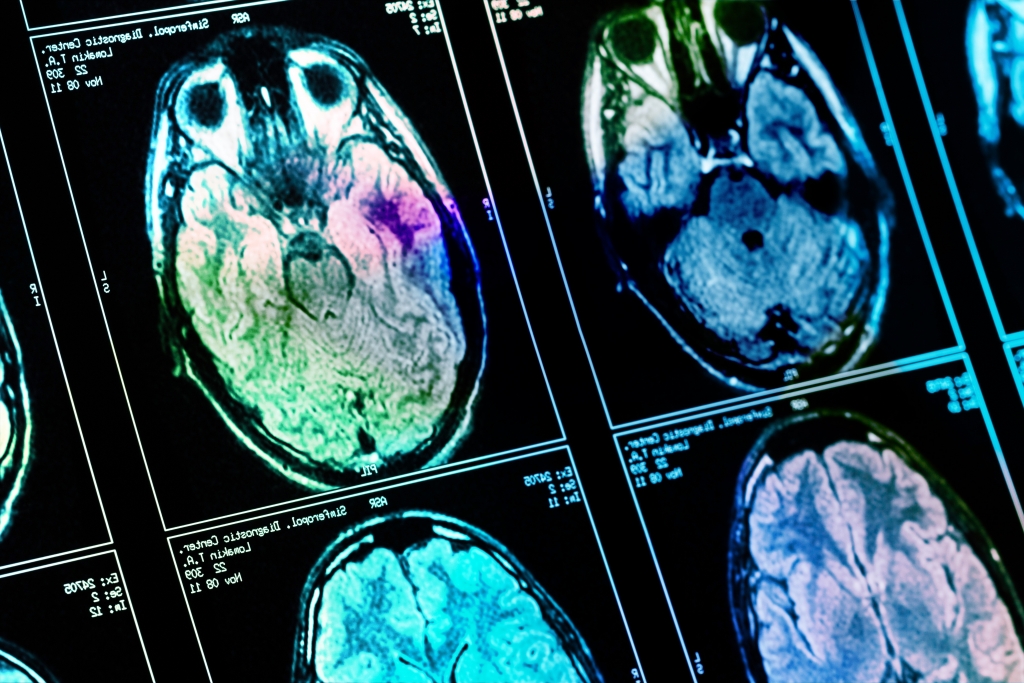

Was dumm macht: Diese fünf Gewohnheiten schränken die Gehirnleistung ein

Nicht nur Demenz kann die kognitive Leistung verschlechtern - auch ganz alltägliche Gewohnheiten können zu Denkproblemen führen. Welche Verhaltensweisen Sie unbedingt ändern sollten.

Noch immer wissen viele nicht, dass Alkohol nicht nur kurzfristig Einfluss auf das Gehirn und die Wahrnehmung hat. Wissenschaftler sind sich einig, dass bereits ein moderater aber regelmäßiger Konsum das Gehirn nachhaltig schädigt. Bei starken Trinkern stellte man in einer Untersuchung an fast 1.800 Verstorbenen fest, dass die Wahrscheinlichkeit für Gefäßschäden im Gehirn um 133 Prozent erhöht war.

Auch ehemalige Trinker hatten eine um 89 Prozent erhöhte Wahrscheinlichkeit als Menschen, die keinen Alkohol tranken. Zudem kommt es häufiger zu Schäden im Gehirn durch die sogenannten Tau-Fibrillen: Diese werden unter anderem mit Alzheimer in Verbindung gebracht und treten bei Trinkern 41 Prozent häufiger auf - ehemalige waren immer noch zu 31 Prozent häufiger betroffen.